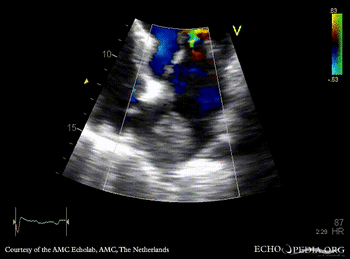

Tumor growing into the left atrium

Courtesy of: AMC Echolab, AMC, The Netherlands

A4CH: tumor growing from pulmonary vein into the left atrium in patient with lung carcinoma A4CH, zoom